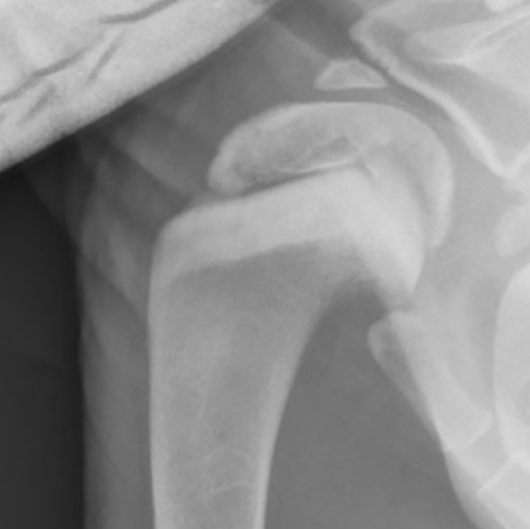

개홍역의 골격계 후유증

보통 후유증으로 틱장애를 가진 신경증상, 치아 애나멜층의 결손등이 거론되는데 방사선상에서 metaphysis의 sclerosis가 유발되는 사례에 대한 보고이다.

참고하고 성견에서 방사선상 이런 병변이 관찰된다면 어린시절 홍역에 감염되었을 가능성이 있는것으로 보고 신경계나 심혈관계 이상에 대한 진단 접근을 해야 할것으로 보인다.